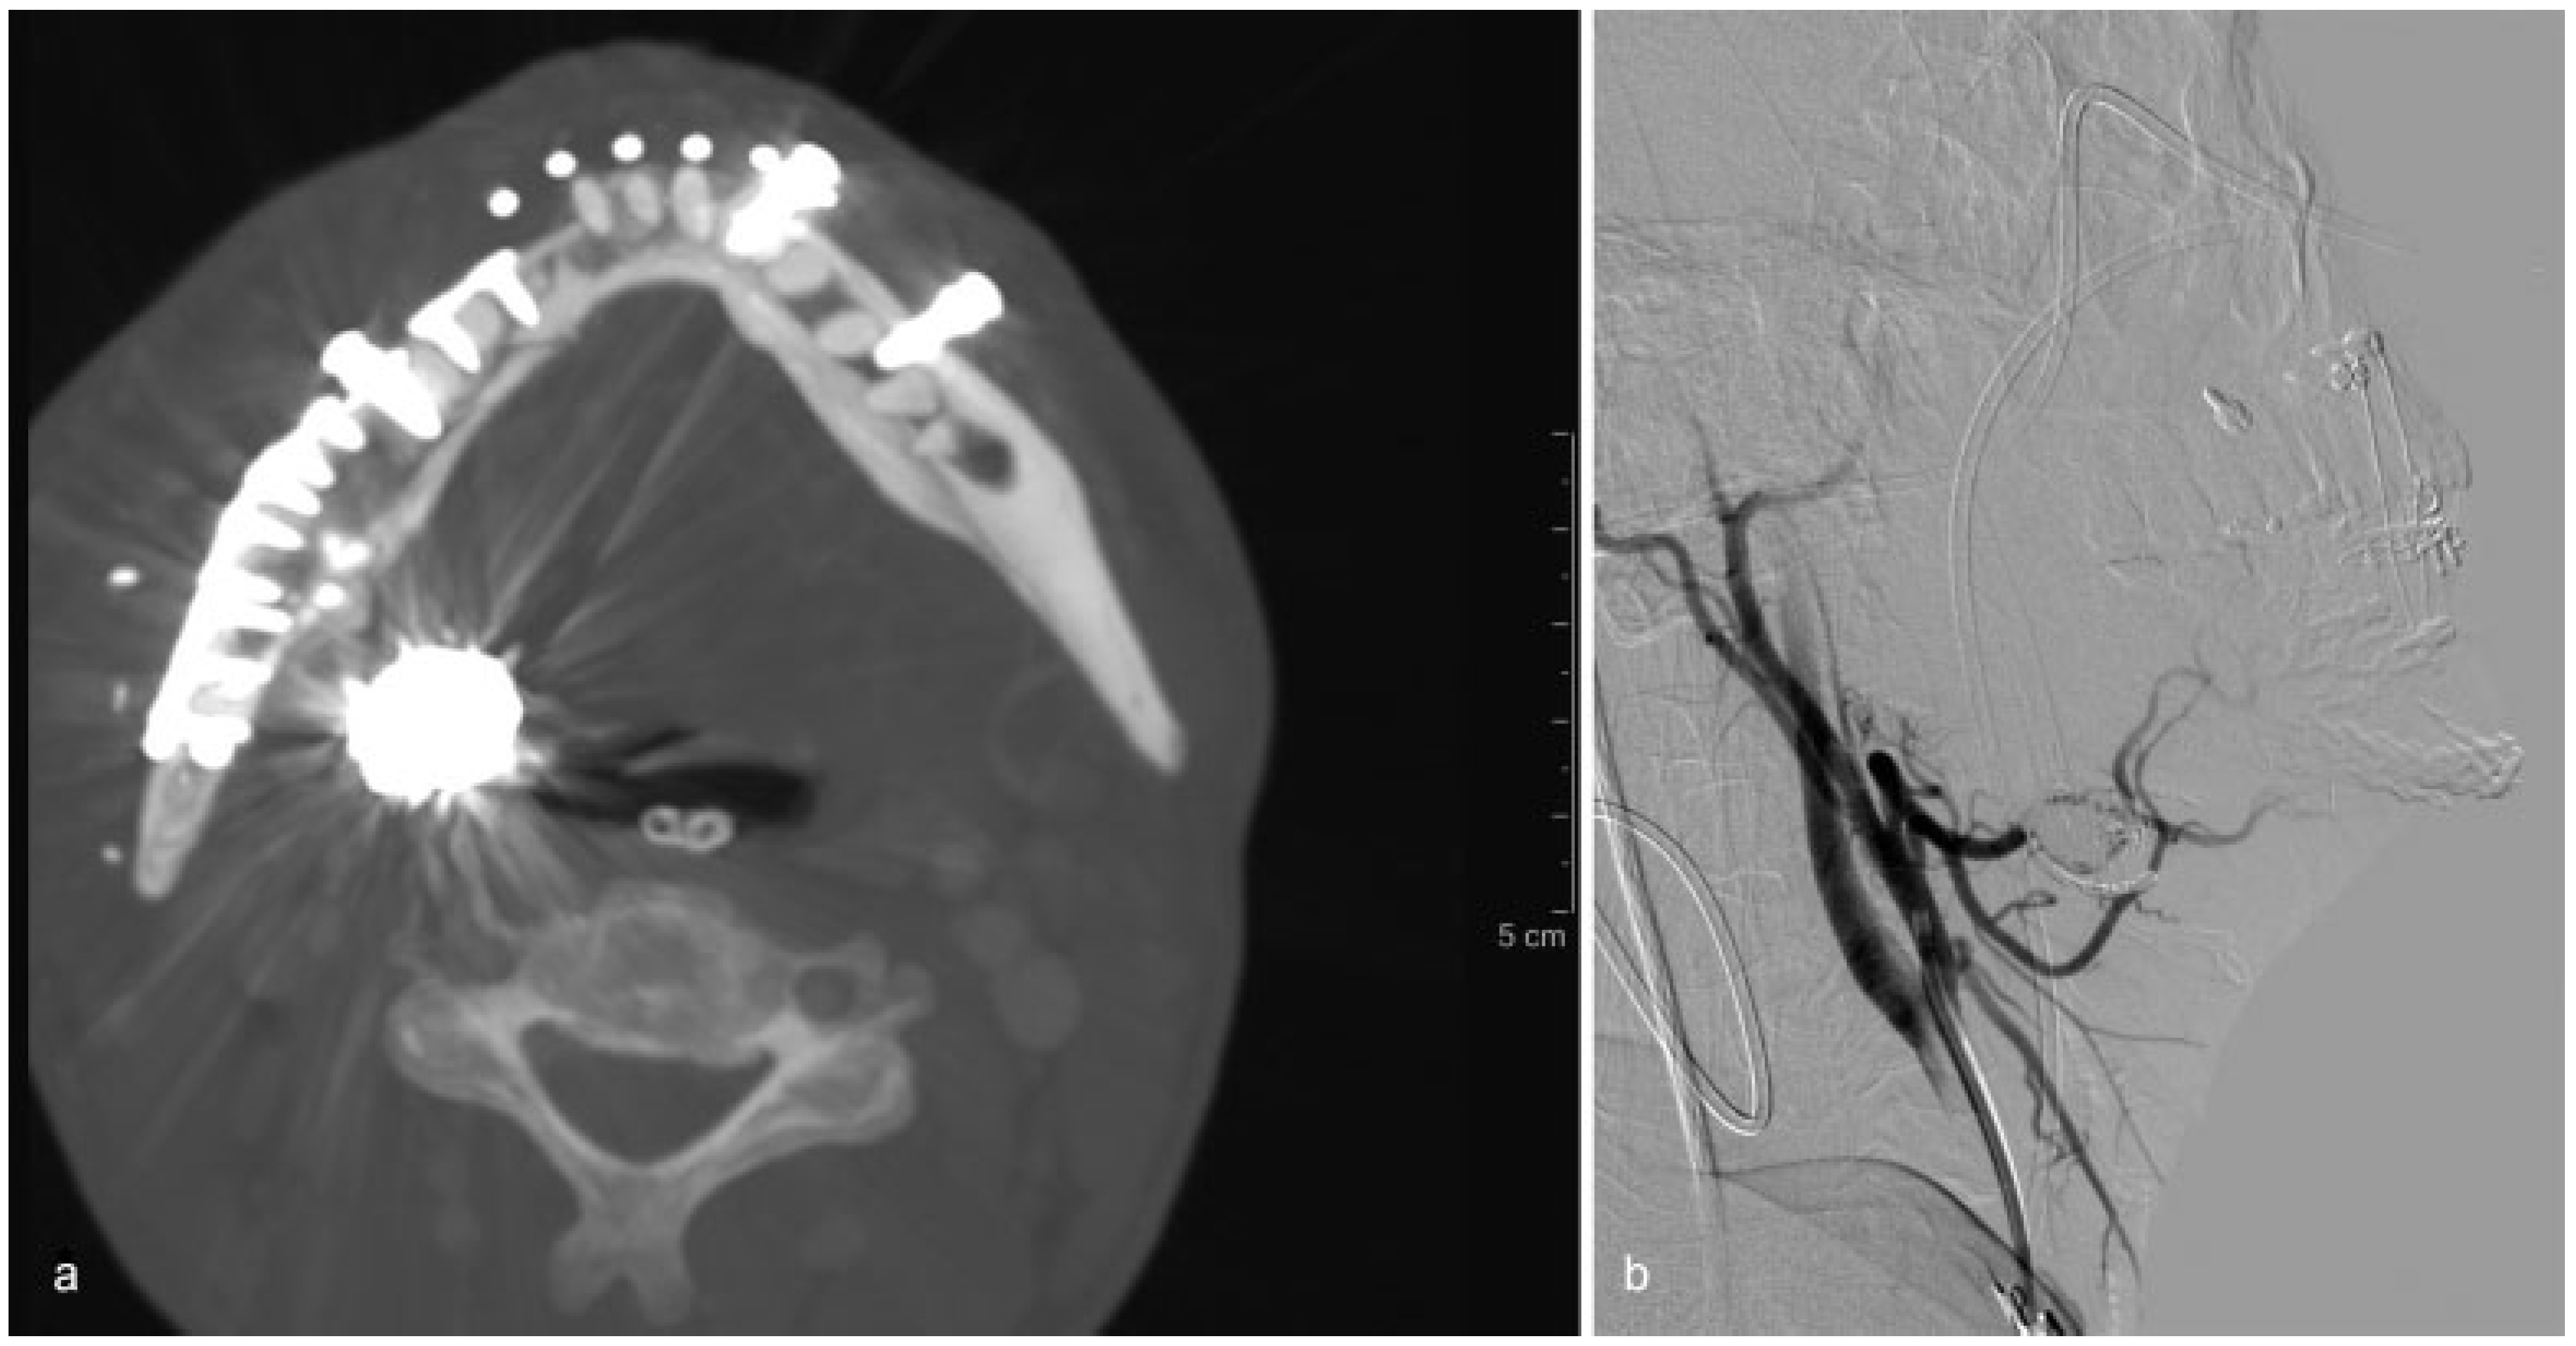

A 45-year-old otherwise healthy male patient was brought to the emergency room following facial trauma at his workplace. The patient had been struck on the right hemiface by the hook of an industrial chain and lost consciousness. The helicopter medical team performed a cricothyroidotomy to secure the airway, and the transferred patient was managed and stabilized by the emergency physician according to our trauma protocol. On arrival, massive arterial and venous bleeding from the lower facial third and oral cavity was temporarily controlled with compression. A facial CT scan showed a severely comminuted, displaced right mandibular fracture and associated hematoma (

Figure 1b,c). The head CT was negative for intracranial bleeding or fracture. The patient was urgently taken to the operating room to stop the facial bleeding, washout and debride the injury site, open reduce and internally fixate the mandibular fracture, and provide soft-tissue coverage with local tissue.

Intraoperative details included the application of Arch bars and mandibular fixation of all fracture fragments with a 2.0-mm reconstructive plate. Dentoalveolar fractures were meticulously fixated with miniplates. Occlusion was restored. Intraoral lacerations, including a significant tongue injury, were repaired. The patient was admitted to the ICU postoperatively.

The immediate postoperative course was uneventful, until unprovoked massive intraoral bleeding on postoperative day 14, required an urgent return to the operating room. After initial control of bleeding, the patient underwent intraoperative angiography that diagnosed a 25-mm pseudoaneurysm arising 10 mm distal to the origin of the right lingual artery (